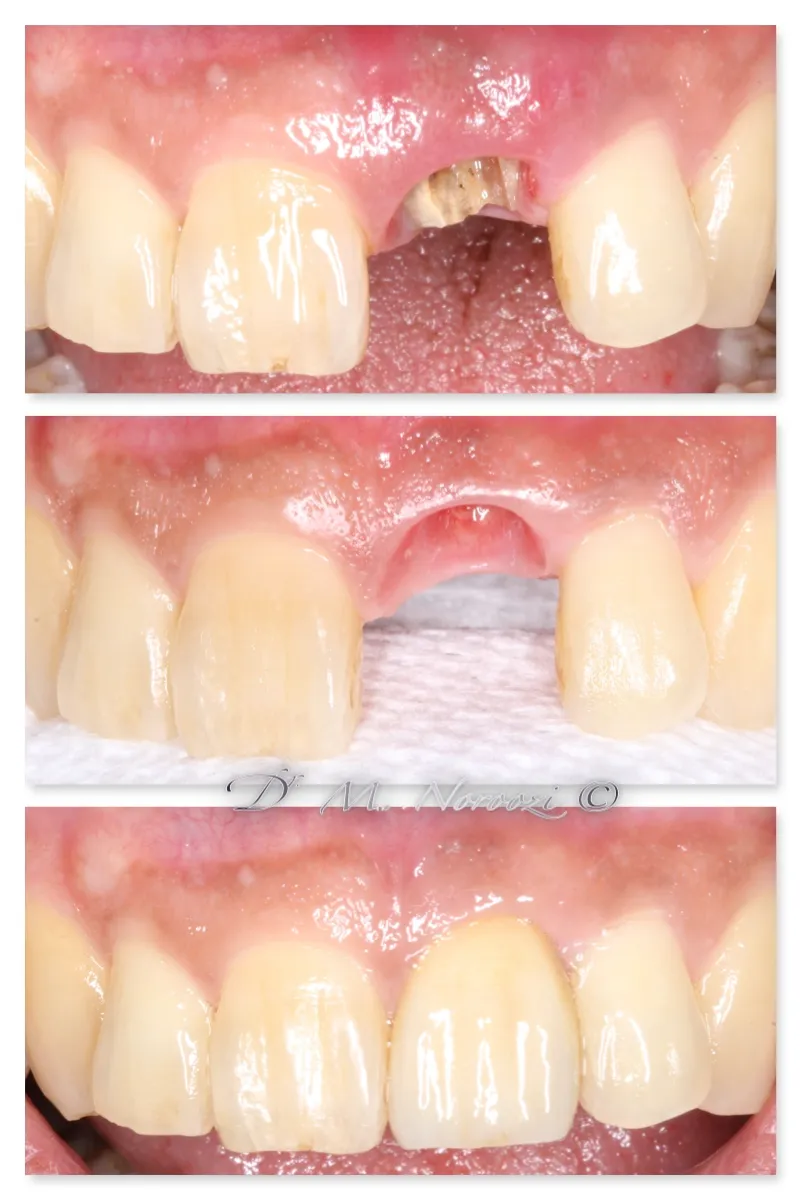

Before & Afters of Dental Implant Patients

Complete Dental Implant Cases Gallery

• During the first stage of surgery, your dentist or specialist will put a dental implant into your jawbone beneath the gum tissue. The gum tissue is then stitched back into place. As the tissue heals, the implant will bond with the bone and attach to the gum. It can take several months to heal.

• During the second stage of surgery and once the tissue is healed, your dentist or specialist will attach an abutment to the implant. An abutment is a post that connects the replacement tooth to the implant. In some cases, the first and second stage of implant surgery may be done in one single stage.

• An artificial replacement tooth is made and your dentist or specialist attaches it to the abutment. It may take several appointments to properly fit the replacement tooth to the abutment.

Surgical advances with SAME-DAY IMPLANTS in Vancouver BC

Using the most recent advances in dental implant technology, Dr. Noroozi is able to place single stage implants. These implants do not require a second procedure to uncover them but may require a minimum of six weeks of healing time before artificial teeth are placed. There are even situations where the implant can be placed at the same time as the tooth extraction and the artificial tooth can be inserted immediately following the implant placement – further minimizing your number of surgical procedures.

General Disclaimer: The results in the photographs are examples only and do not imply any certainty of the result of a procedure, and all outcomes are subject to the circumstances of the individual patient.